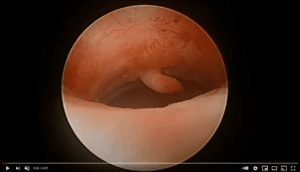

MyoSure® Tissue Removal System

MyoSure® Tissue Removal